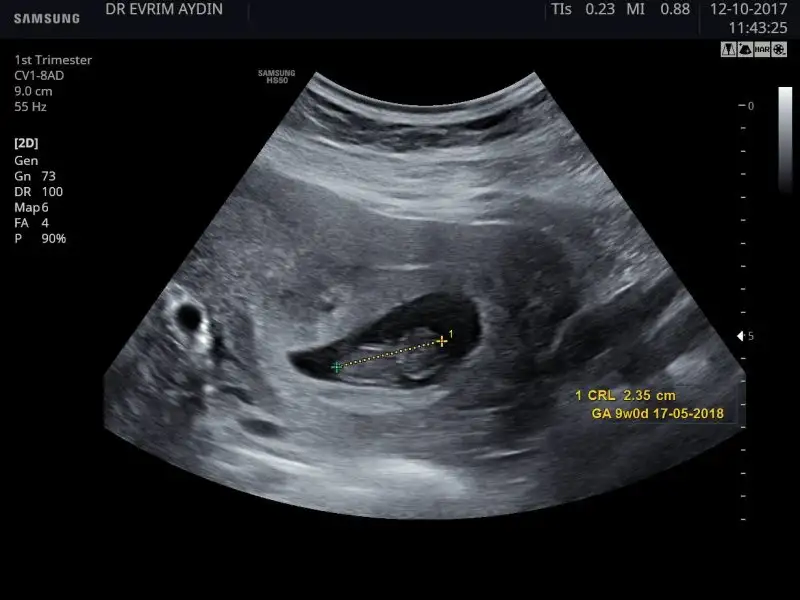

Ay canım maşallah ona valla ben hiç yorum yapamıyorum ama arkadasın dediği gibi benimde tam terste duruyo ben gecen persembe gittim 9+0 cıktı 6 gündü fark yakalamıs gibi duruyo 3 güne inmiş adetimle farkıTeyzoslar yorumlayabilecekmisiniz bakalım bebeğimi

OyyyOyyy maşallahhh. cinsiyet konusunda yorum yapamicam yalnız çünkü hiç anlamıyorumTeyzoslar yorumlayabilecekmisiniz bakalım bebeğimi

Ayy aynı gün randevumuzYa ben foto hiç koymamıştım :) 12 gün önce gittiğim ultrason fotosunu koyayım. Tam 9 haftalıktı.

Benimki neye benziyor kıza mı erkeğe mi :))